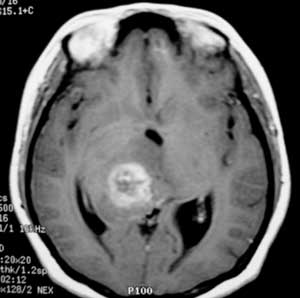

女性,28岁。头痛请会诊

右侧丘脑类圆形等t1,长t2病灶,t1增强明显强化。

女性,28岁。头痛请会诊。

考虑:①丘脑胶质瘤可能大。②脑积水。

t1等信号内出现点状高信号,考虑为出血灶,肿块内侧可见弧形低信号,为脑积液影。长t2,其内有混杂信号,周壁强化明显,内不规则强化,生长位置似在右侧丘脑,又似在来源于侧脑室,故脉络丛乳头状瘤不排外。